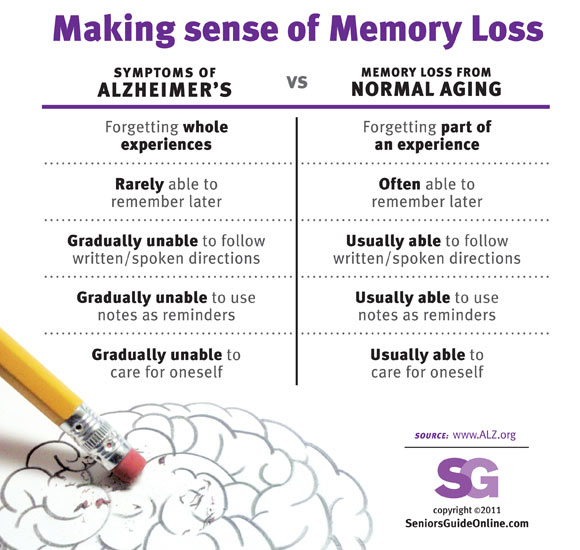

What is Dementia? Dementia vs Alzheimer’s Disease